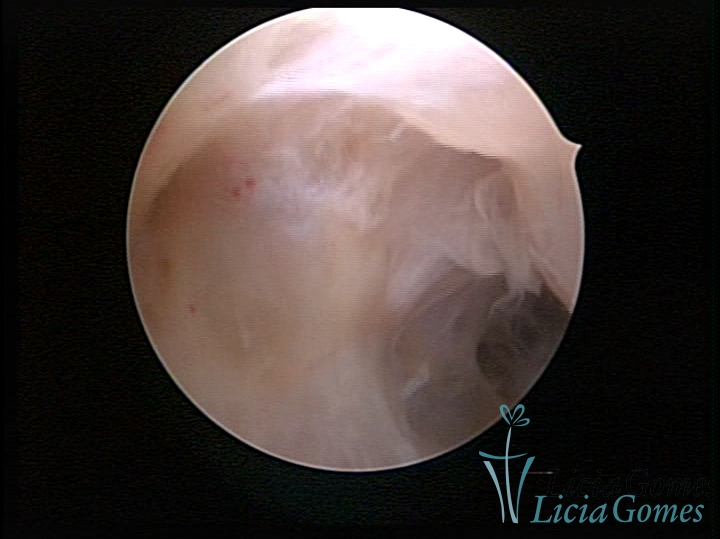

• SINÉQUIA TIPO FIBROMUSCULAR

As Sinéquia uterinas são cicatrizes (aderências) entre as superfícies das paredes uterinas, que podem ocorrer após manipulação cirúrgica, ou curetagem uterina, ou após um processo inflamatório na cavidade uterina (endometrite), podendo levar a alterações menstruais, infertilidade, e complicações obstétricas, como abortamento, parto prematuro.